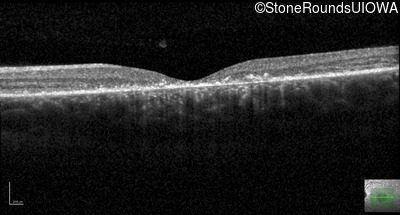

Optical Coherence Tomography - Right - 20/25 +1 sc

Exemplar / OCT Stack